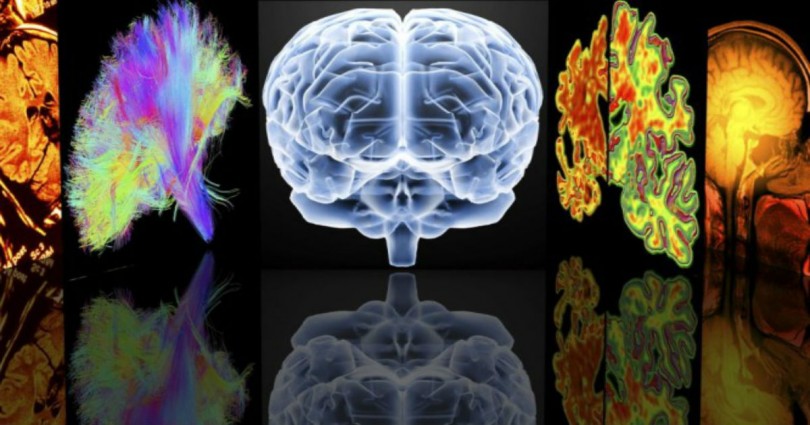

Πώς προκαλείται και τι προκαλεί η Σκλήρυνση Κατά Πλάκας

Στην Σκλήρυνση Κατά Πλάκας, η βλάβη στην επικάλυψη μυελίνης γύρω από τις νευρικές ίνες στο κεντρικό νευρικό σύστημα και στις ίδιες τις νευρικές ίνες παρεμβαίνει στην μετάδοση των νευρικών σημάτων μεταξύ του εγκεφάλου, του νωτιαίου μυελού και του υπόλοιπου σώματος. Αυτά τα προβληματικά νευρικά σήματα προκαλούν τα συμπτώματα της ΣΚΠ, τα οποία διαφέρουν από το ένα άτομο στο άλλο και, με την πάροδο του χρόνου, αλλάζουν για τον κάθε ασθενή, ανάλογα με το πού και πότε λαμβάνει χώρα η βλάβη.

Η διάγνωση της ΣΚΠ απαιτεί να επιβεβαιωθούν συμπτώματα σε τουλάχιστον δύο περιοχές του κεντρικού νευρικού συστήματος, τα οποία έχουν συμβεί σε διαφορετικές χρονικές στιγμές.